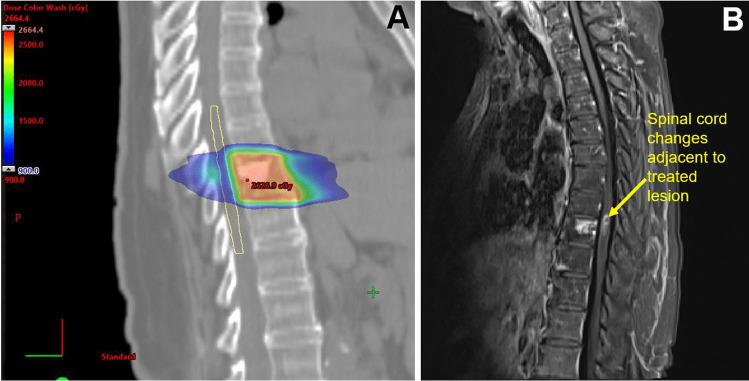

We examine the potential for curative approaches among metastatic breast cancer (MBC) patients by exploring the recent literature on local ablative therapies like surgery and stereotactic body radiation therapy (SBRT) in patients with oligometastatic (OM) breast cancer. We also cover therapies for MBC patients with oligoprogressive (OP) disease.

Surgery and SBRT have been studied for OM and OP breast cancer, mainly in retrospective or non-randomized trials. While many studies demonstrated favorable results, a cooperative study and single-institution trial found no support for surgery/SBRT in OM and OP cases, respectively.

While there is interest in applying local therapies to OM and OP breast cancer, the current randomized data does not back the routine use of surgery or SBRT, particularly when considering the potential for treatment-related toxicities. Future research should refine patient selection through advanced imaging and possibly explore these therapies specifically in patients with hormone receptor-positive or HER2-positive disease.